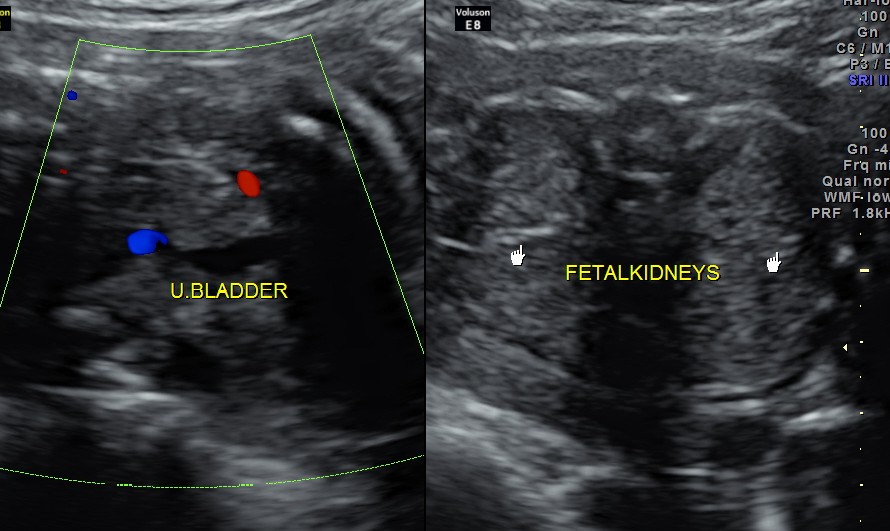

https://kriznanultrasoundimages.com/2013/05/12/tetralogy-of-fallot-tof/ at this time there was a revision of the cardiac findings : LEFT ATRIAL ISOMERISM WITH TETRALOGY OF FALLOT The irregular rhythm was not made out now. Apart from this the foetus has symmetrical IUGR and oligohydramnios Now the child was brought when she was 51 days old . She was born prematurely at 33 weeks of gestation . She had been seen at three higher institutions . The paediatric cardiologist has given a working diagnosis of CONO TRUNCAL VSD. But the catch was that the child had renal dysfunction with s .creatinine around 2 mgms and the ultrasound could not visualise the left kidney. The right kidney was reported to be hyperechoic . The following 2 pictures were of the fetal kidneys , as seen during the scan earlier.

The following two pictures show the hyperechoic kidneys of the child with mild pelvi calyceal dilatation . The kidneys were picked up only with the 11 mhz transducer.